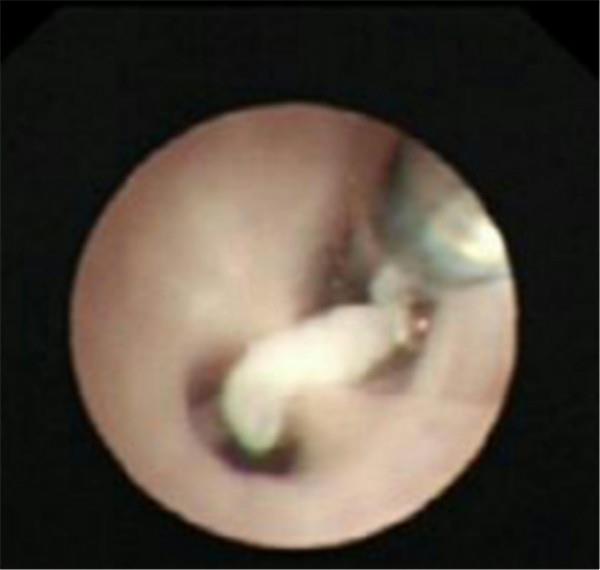

檢查中氣道內(nèi)情景

肺泡內(nèi)灌洗出來的渾濁液體